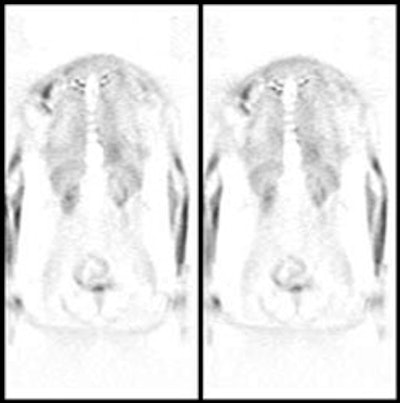

|

Myocardial activity: Myocardial uptake can be very variable. The patient on the left below had a glucose level of 97 prior to FDG injection. Despite the normal serum glucose, note the intense cardiac activity in this patient. The patient on the right was a diabetic patient with a blood glucose of 169- note that there is no myocardial uptake in this patient despite the elevated glucose level. |